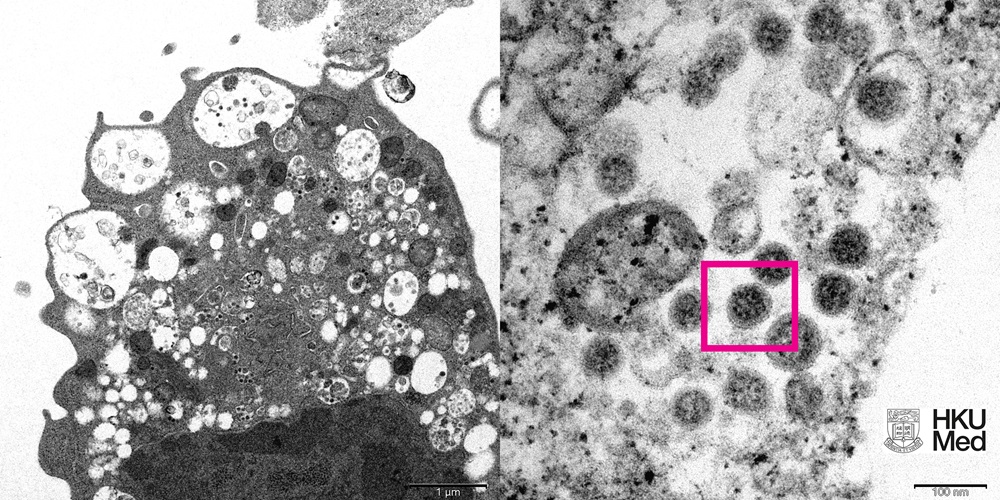

Hình ảnh độ phóng to thấp (trái) và cao của biến thể Omicron dưới kính hiển vi điện tử - Ảnh: HKU